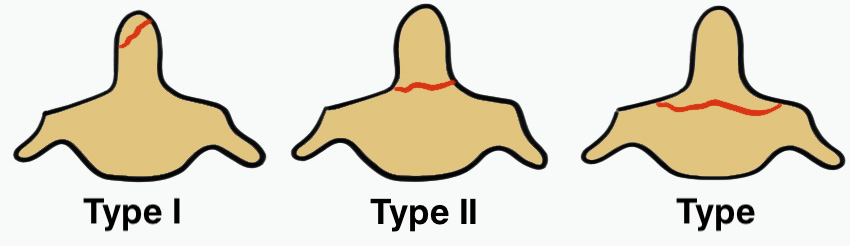

Classification Anderson & D'alonzo

Type 1

Tip avulsion

- alar ligament avulsion

- fracture off one side of tip of odontoid process

- rare

Type 2

Fracture of base of odontoid process

- most common type

- > 50%

Type 3

Fracture through body of axis